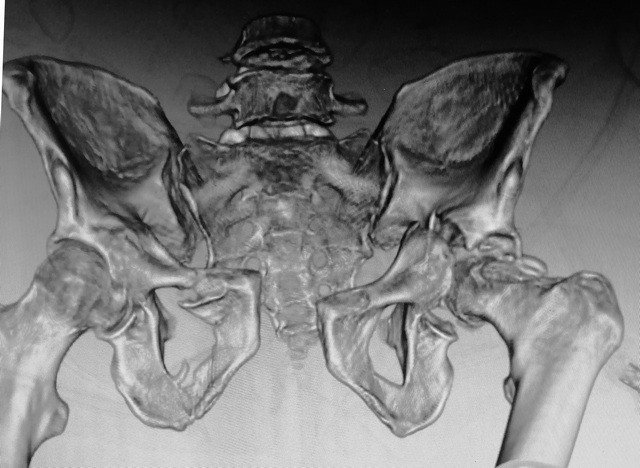

Мужчина 50 лет. Социальный, активный. Политравма 6 сут назад.

Со стороны живота - разрыв брыжейки, сейчас все ОК. Стабилен, в сознании, Hb 75. Таз на фото. Мой план: 1. IS справа, 2. поперечник и задняя стенка задним доступом, 3. передние отделы. Хотелось бы услышать ваше мнение, возможно рациональнее будет что-то другое?PS рентгена нет, был body scan

Подвздошным доступом открытая репозиция, фиксация крестцово-подвздошного сочленения. Репозиция, фиксация лонных костей, передней колонны пластинами или канюлированными винтами малминвазивно, фиксация лонного сочленения. Вторым этапом (через 2-3недели или позднее с учётом состояния пациента) тотальное эндопротезирование левого тазобедренного сустава с использованием укрепляющего кольца типа Мюллера, возможно, костной пластики заднего края вертлужной впадины.